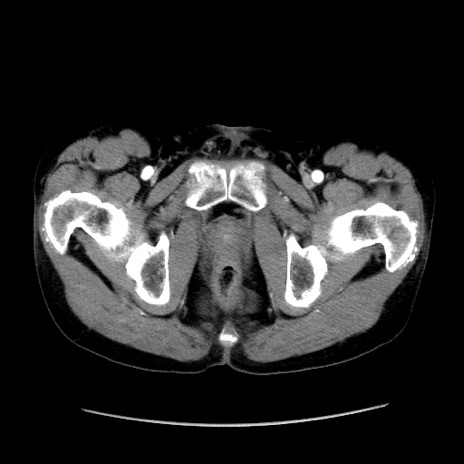

冠状断像

症例37(横断像)

【症例】40歳代 男性

【主訴】腹痛

【現病歴】4時間ほど前に電車に乗車中に臍部上より腹痛出現。徐々に増悪し起立困難となり、救急外来受診。生ものは数日食べていない。今朝お雑煮を食べた。

【身体所見】BT 36.8℃、BP 117/84mmHg、HR 91/min、SpO2 97%、苦悶様、腹部:臍上部広範囲圧痛あり、反跳痛±

【データ】WBC 8100、CRP 0.03